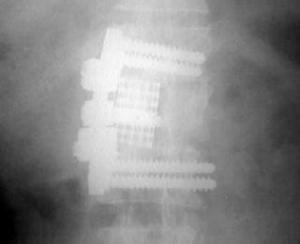

Radiologías del Pos - operatorio

Radiología Pos - operatorio mediato:

Aspecto radiológico final de la artrodesis de columna T12 - L1 - L2